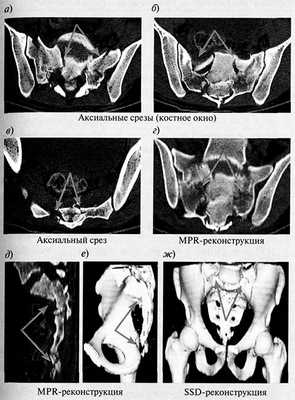

Переломы крестца представлены на рис. 1.

Рис. 1. Многооскольчатый перелом (стресс-перелом) крестца и копчика. КТ

При спиральной компьютерной томографии нижнепоясничного, крестцового отделов позвоночника и копчика определяются перелом копчика, многооскольчатый перелом боковых масс крестца с нарушением целостности крестцовых отверстий со смещением кпереди и книзу тел S1 и S2 позвонков (стрелки).